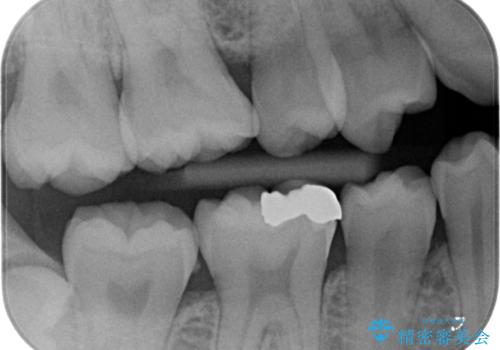

メタルを除去し、拡大鏡下で虫歯がない事を確認しe-maxインレーで治療を行いました。

適合が良い詰め物が入りました。